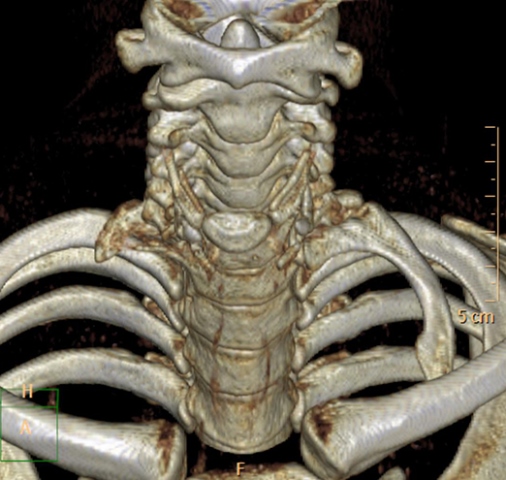

ب) دنده گردنی چیست؟

گاهی اوقات پایینترین مهره گردن یعنی مهره هفتم هم یک دنده دارد که البته به اندازه دنده های سینه ای نیست و از آنها کوچکتر است. پس این دنده در بالای دنده اول سینه ای قرار میگیرد. به این دنده اضافی دنده گردنی میگویند و از هر 200 انسان در یک نفر وجود دارد. پس این انسان ها بجای 12 جفت دنده 13 جفت دنده دارند. وجود دنده گردنی ممکن است باعث ایجاد درد در گردن و دست و بیحسی یا مور مور شدن دست شود. دنده گردنی میتواند در یک طرف گردن باشد و یا میتواند دو طرفه باشد . همانطور که گفتیم یک سر این دنده به مهره هفتم گردنی متصل شده است ولی سر دیگر آن معمولا آزاد است. البته گاهی اوقات سر دیگر آن با دنده اول سینه ای مفصل میشود و یا گاهی اوقات از سر این دنده گردنی یک نوار بافتی محکم خارج شده و به دنده اول متصل میشود .

اهمیت دنده گردنی چیست؟

برای درک اهمیت دنده گردنی باید ابتدا بدانیم فضای خروجی سینه یا توراسیک اوتلت چیست : در جلو و بالای دنده اول، استخوان ترقوه قرار گرفته است. بین دنده اول و استخوان ترقوه فضایی وجود دارد که به آن فضای خروجی سینه یا توراسیک اوتلت میگویند. از لحاظ آناتومی این فضا در بین قاعده گردن و زیر بغل شما قرار گرفته است. در نزدیکی این فضا عضلاتی هم به نام عضلات اسکالنScalenus muscles قرار دارند. اهمیت این فضا در اینست که عروق و اعصاب مهمی از آن عبور میکنند.

اعصاب مهمی که از دو طرف مهره های گردنی خارج میشوند به هم میپیوندند و ایجاد شبکه ای را میکنند که به آن شبکه بازویی Brachial plexus میگویند از این شبکه بازویی اعصاب مهمی منشعب میشود که حس و حرکت کل اندام فوقانی را ایجاد میکنند. این شبکه بازویی از توراسیک اوتلت عبور میکند. همچنین شریان مهمی به نام شریان ساب کلاوین Subclavian یا زیر ترقوه ای از آئورت خارج میشود و از این فضا عبور میکند و سپس به اندام فوقانی رفته و کل اندام را تغذیه میکند. در این فضا وریدی هم به همین نام قرار دارد .

اهمیت این فضای توراسیک اوتلت در بیماری است که به علت تنگ شدن این فضا ایجاد شده و به آن سندرم توراسیک اوتلت Thoracic outlet syndrome میگویند. این فضا به علل مختلفی میتواند تنگ شود. تنگ شدن آن معمولا در طرف راست یا چپ است ولی میتواند دو طرفه هم باشد. بدنبال تنگ شدن این فضا اعصاب شبکه بازویی تحت فشار قرار میگیرند و فشار به این اعصاب، علائمی را برای بیمار ایجاد میکند. گاهی هم ممکن است شریان یا ورید ساب کلاوین هم در این فضا گیر کنند که فشار به آنها هم میتواند علائم دیگری را برای بیمار ایجاد کند

اهمیت دنده گردنی اینست که وجود آن یکی از شایعترین علل ایجاد سندرم توراسیک اوتلت است .

یکی از علل شایع تنگ شدن فضای توراسیک اوتلت، وجود دنده گردنی است. پس اهمیت دنده گردنی اینست که میتواند فضای توراسیک اوتلت را تنگ کرده و به اعصاب یا عروقی که از این ناحیه عبور میکنند فشار ایجاد کند. البته اینطور نیست که هر کسی که دنده گردنی دارد این مشکلات را هم داشته باشد. از هر ده نفری که دنده گردنی دارند فقط در یک نفر آنها به اعصاب یا عروق فشار وارد شده و مشکل دار میشوند .